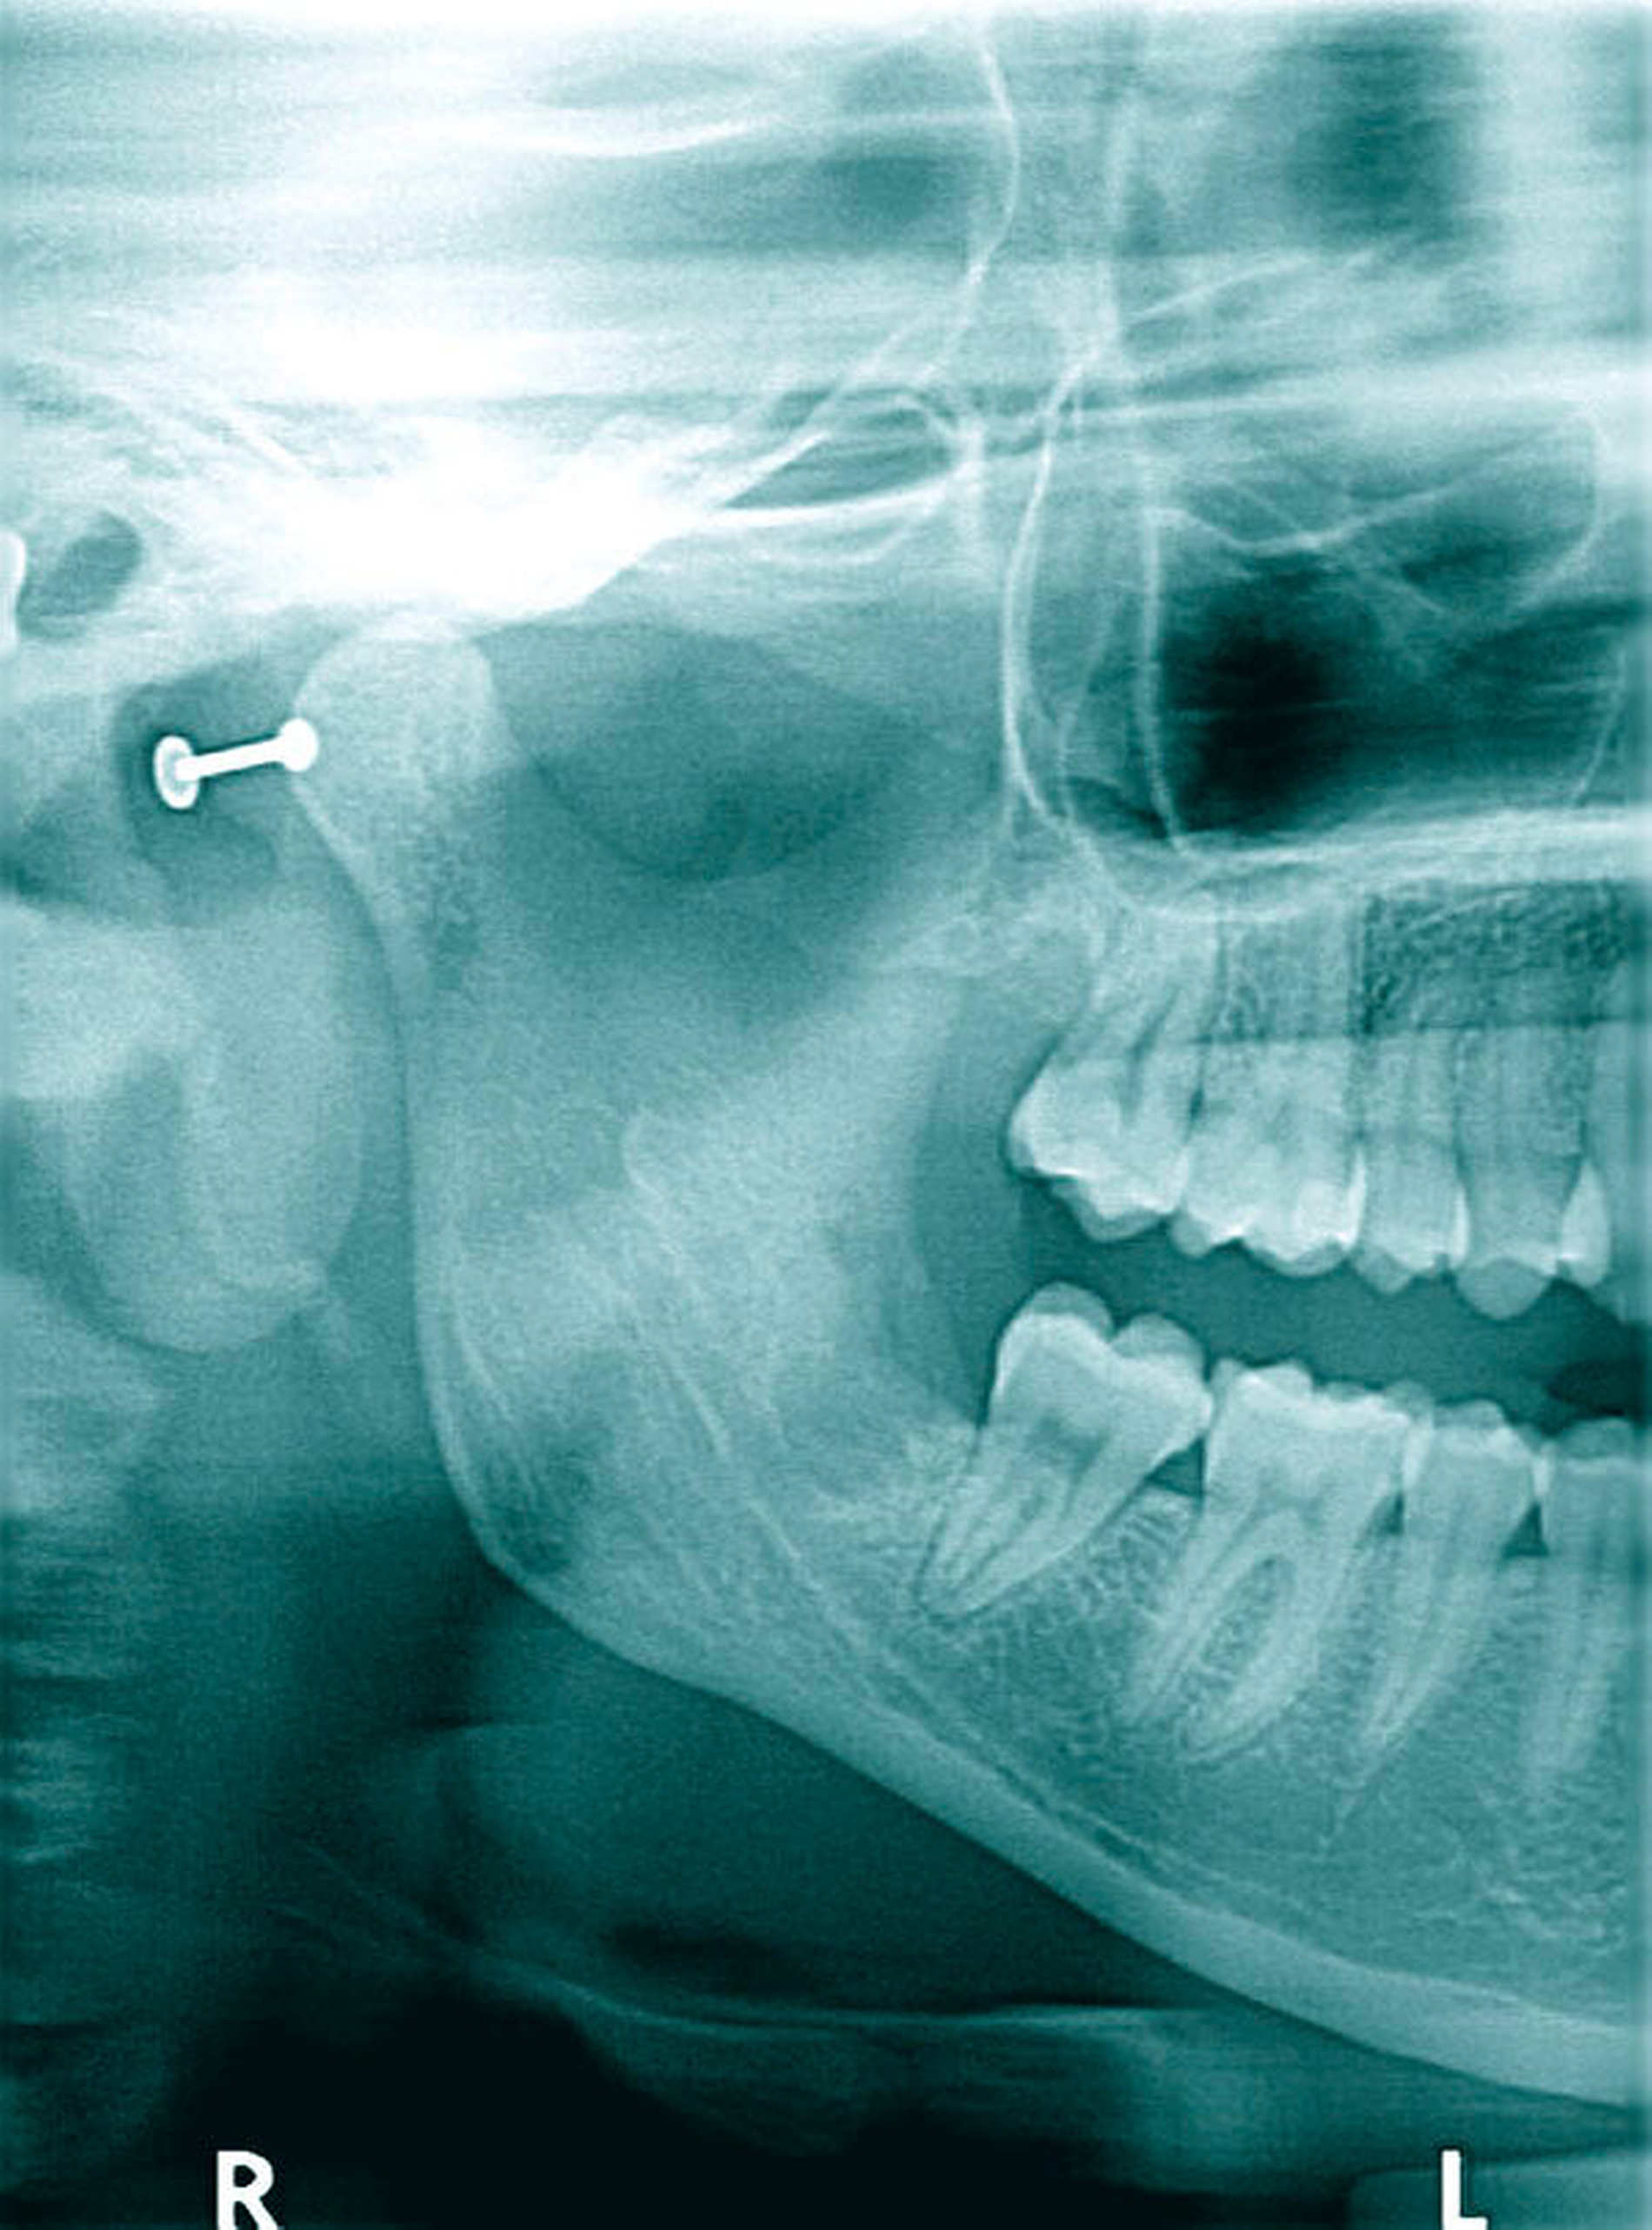

Fünf Monate später wurde die Patientin mit rezidivierenden Wundproblemen in Regio 048 und Zustand nach Wundrevision beim Zahnarzt erneut vorstellig. Ein nun von uns erstelltes Halbseiten-OPG (Abbildung 2) zeigte einen periapikal verbreiterten PA-Spalt des Zahns 47 und eine leere, unscharf begrenzte Extraktionsalveole Regio 048. Wir führten eine erneute ambulante Wundrevision und plastische Deckung durch und rezeptierten ein orales Analgetikum (Novalgin) und ein orales Antibiotikum (Clindamycin). Eine Ultraschalluntersuchung erbrachte lediglich den Verdacht auf reaktive Lymphknoten unterhalb des rechten Kieferwinkels jugulo-digastrisch.